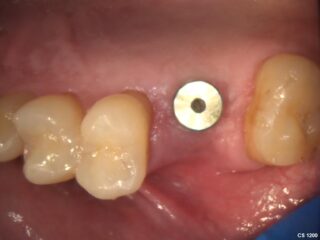

During the healing phase, a small healing cap is used to protect the implant and shape the surrounding gum tissue, preparing the area for the final crown or bridge.

A dental implant, usually made of titanium, is placed into the jawbone. Over time, the implant fuses with the bone to create a solid and stable foundation.